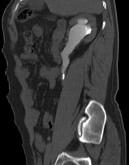

- 多项选择题患者男,36岁, 反复发作的右侧腰背部疼痛伴血尿1年余加重2小时,CT如图所示, 下列说法正确的是 ( )

A、右侧肾盂肾盏扩张

B、右输尿管上段扩张

C、右输尿管内可见沿输尿管走行的高密度影

D、右输尿管结石

E、右输尿管上段钙化